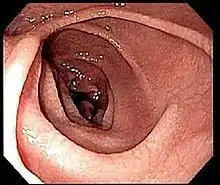

An upper endoscopy with biopsy of the duodenum (beyond the duodenal bulb) or jejunum is performed to obtain multiple samples (four to eight) from the duodenum. Not all areas may be equally affected; if biopsies are taken from healthy bowel tissue, the result would be a false negative.[40] Even in the same bioptic fragment, different degrees of damage may be present.[16]

Most people with coeliac disease have a small intestine that appears to be normal on endoscopy before the biopsies are examined. However, five findings have been associated with a high specificity for coeliac disease: scalloping of the small bowel folds (pictured), paucity in the folds, a mosaic pattern to the mucosa (described as a "cracked-mud" appearance), prominence of the submucosa blood vessels, and a nodular pattern to the mucosa.[95]